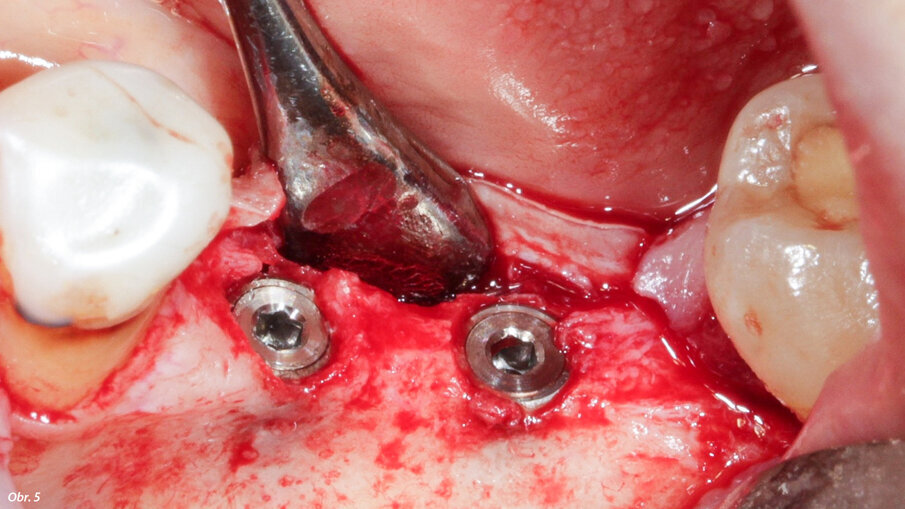

Malá tloušťka zbytkové kosti ve vestibulární oblasti implantátů.

Kořeny byly vytvarovány tak, aby pasovaly do místa defektu a jsou

v místě transplantace zajištěny osteosyntetickými šroubky.